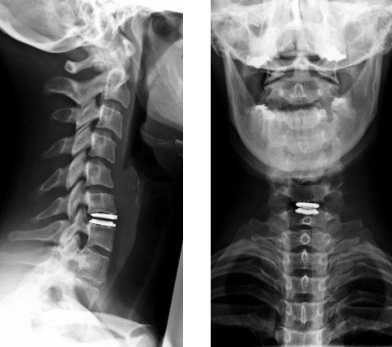

Полную протяженность шейного отдела позвоночника можно увидеть только в положении сбоку. Если же снимок делается в прямой проекции, тень от нижней челюсти будет закрывать первый и второй позвонки. Чтобы получить качественное изображение, потребуется сделать прицельный снимок через открытый рот пациента.

При явных признаках смещения одного или нескольких позвонков шейного отдела, врач назначает рентгенографию позвоночника (спондилографию). При вероятном смещении Атланта (первого позвонка) рентгенография производится через рот.

- Рентгенографии ШОП. Рентген шейного отдела позвоночника с захватом затылочной кости в прямой и боковой проекциях позволяет визуализировать место сращения. На стандартных и функциональных рентгенограммах часто обнаруживаются признаки нестабильности СIV-СV и СV-СVI, которой сопровождается ассимиляция атланта: изменение высоты межпозвонковых дисков, смещение позвонков и нарушение параллельности их суставных поверхностей.

Основным инструментальным методом диагностики подвывиха шейных позвонков является рентгенография позвоночника с использованием как стандартных (боковой и прямой), так и дополнительных проекций: косых снимков, снимков через рот, рентгенограмм в положении разгибания и сгибания шеи. Перечень дополнительных проекций, назначаемых в каждом конкретном случае, определяется с учетом предположительного уровня повреждения. Наряду с рентгенографией могут быть назначены КТ и МРТ.